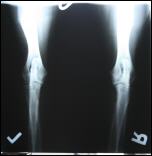

Allys Hüften

HD: A2/A2